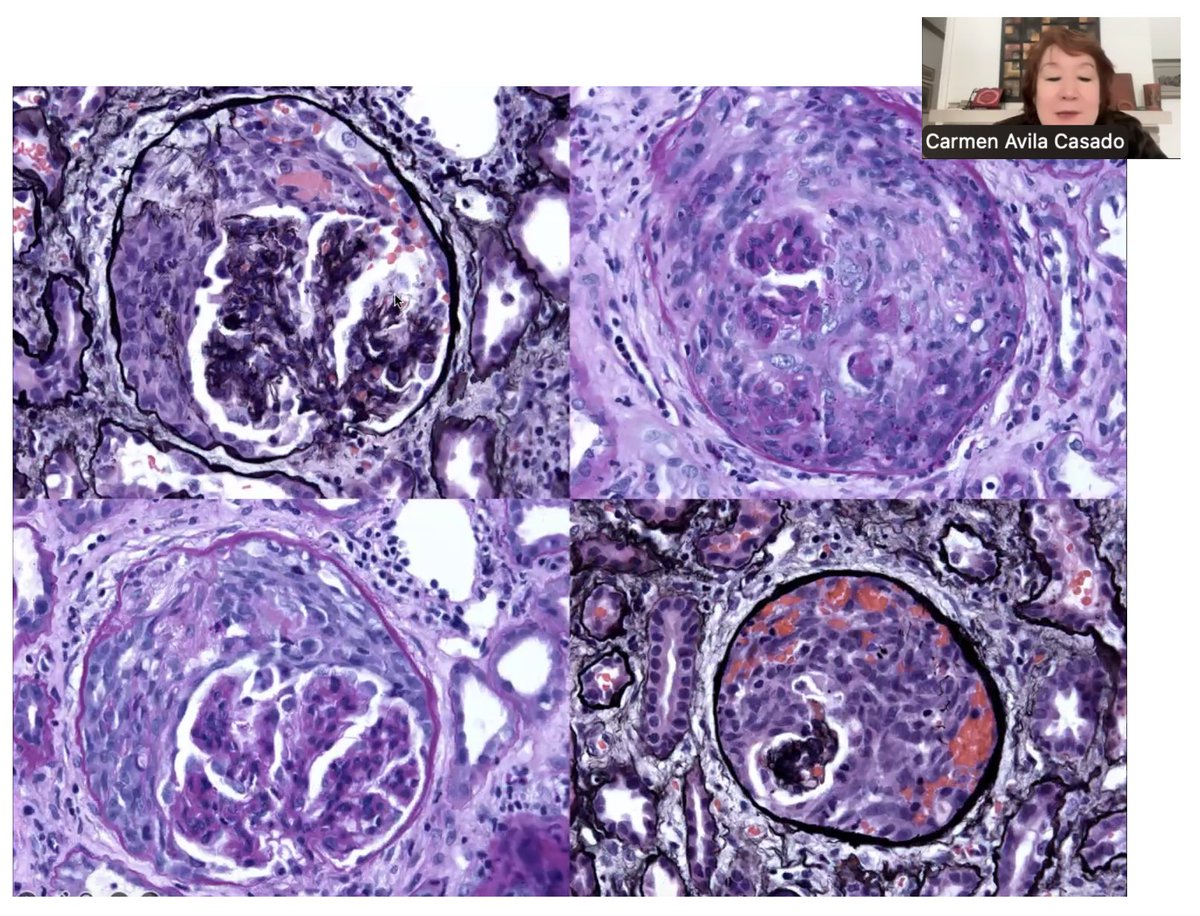

Check out our editorial "Rituximab in Podocytopathies: A Promise Realized?" in March 2025 edition of ASN Kidney News @asnpublications